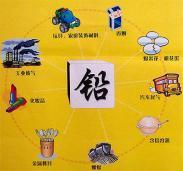

铅中毒

628健康网为您分享有关铅中毒的症状,铅中毒的治疗方法,铅中毒的预防知识,铅中毒的症状图片,铅中毒吃什么药,铅中毒怎么治...